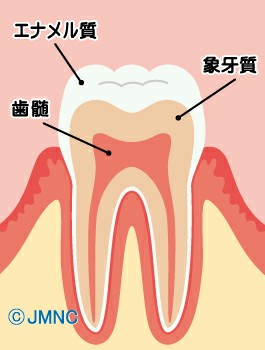

まずは、健康な歯の図です。

歯は三層に別れていて

- エナメル質

- 象牙質

- 歯髄

と呼ばれ、どこまで到達したか、が分類の基準となります。

C0:白濁もしくは着色のある歯

C1:エナメル質が脱灰した初期の虫歯

C2:象牙質まで進行した虫歯

C3:歯髄まで進行した虫歯

C4:歯の根だけが残った状態